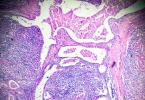

左侧精索静脉稍曲张在男性中较为常见,很多人会担心其严重程度。其实这需要从多方面来综合判断。接下来为大家详细介绍相关内容。Ⅰ级曲张的特征静脉直径:左侧精索静脉稍曲张通常属于Ⅰ级曲张,此时静脉直径0.5mm、出 ...